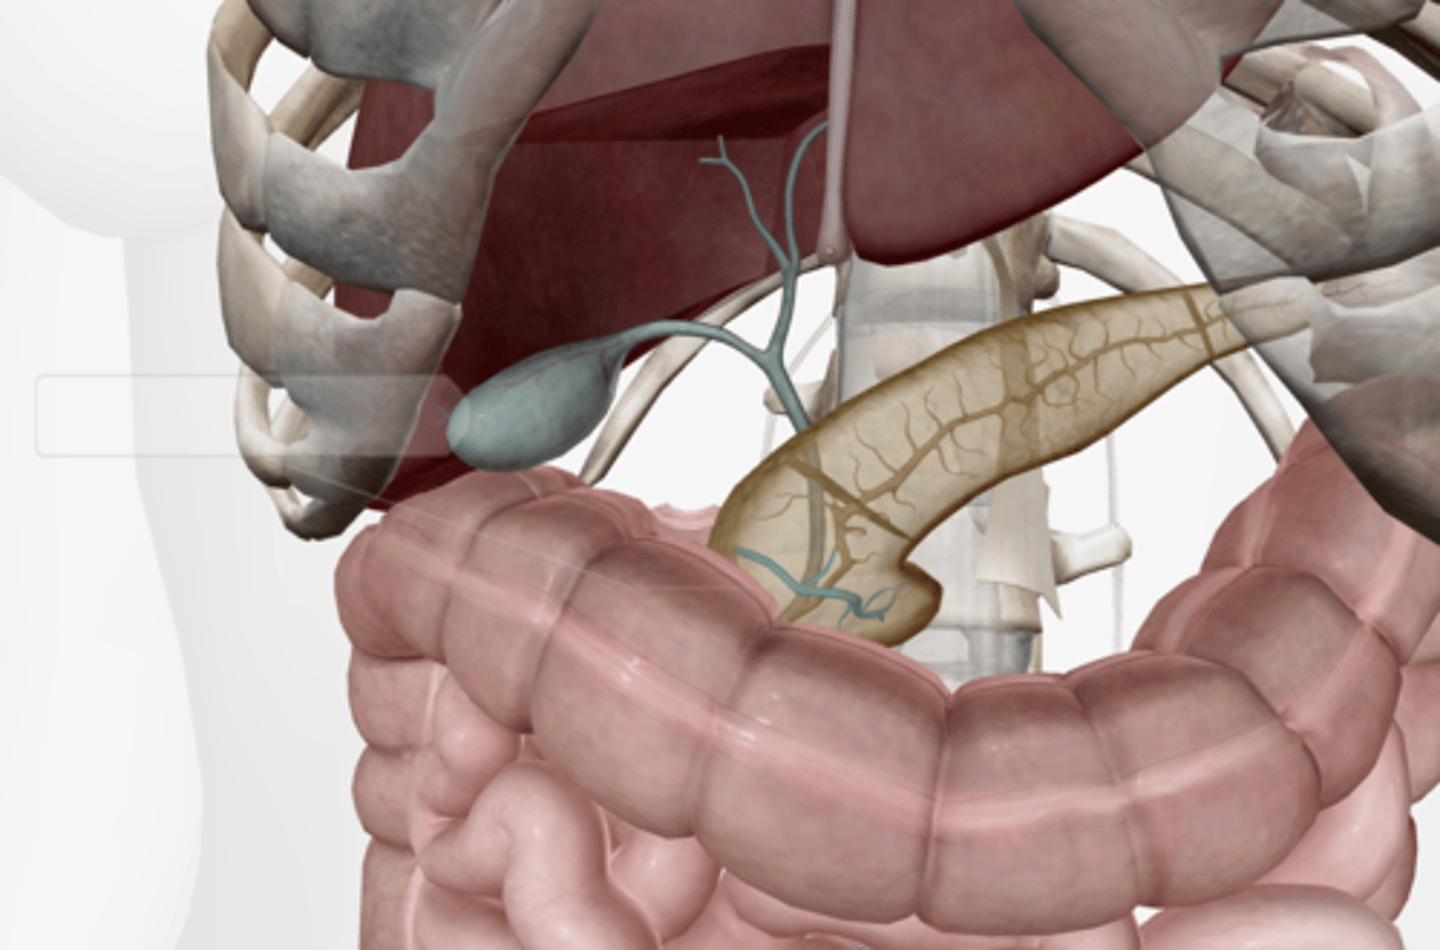

Gallbladder

Cystic duct

Common hepatic duct

Common bile duct

Pancreas

Main pancreatic duct (duct of Wirsung)

Accessory pancreatic duct (duct of Santorini)

Liver

Hepatic artery & vein

Falciform ligament

Duodenum